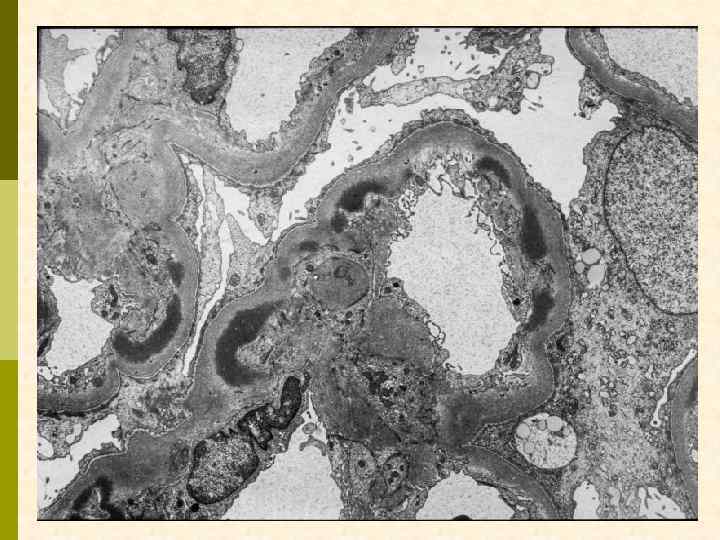

ХРОНИЧЕСКАЯ ТРОМБОТИЧЕСКАЯ МИКРОАНГИОПАТИЯ Ранние признаки: набухание эндотелиоцитов, потеря фенестр, отделение эндотелия от мембраны, заполнение субэндотелия электронно-прозрачным материалом (белки, участвующие в процессе свертывания + клеточный детрит), новообразование базальных мембран под смещенным эндотелием. Нефробиоптат больного первичным антифосфолипидным синдромом